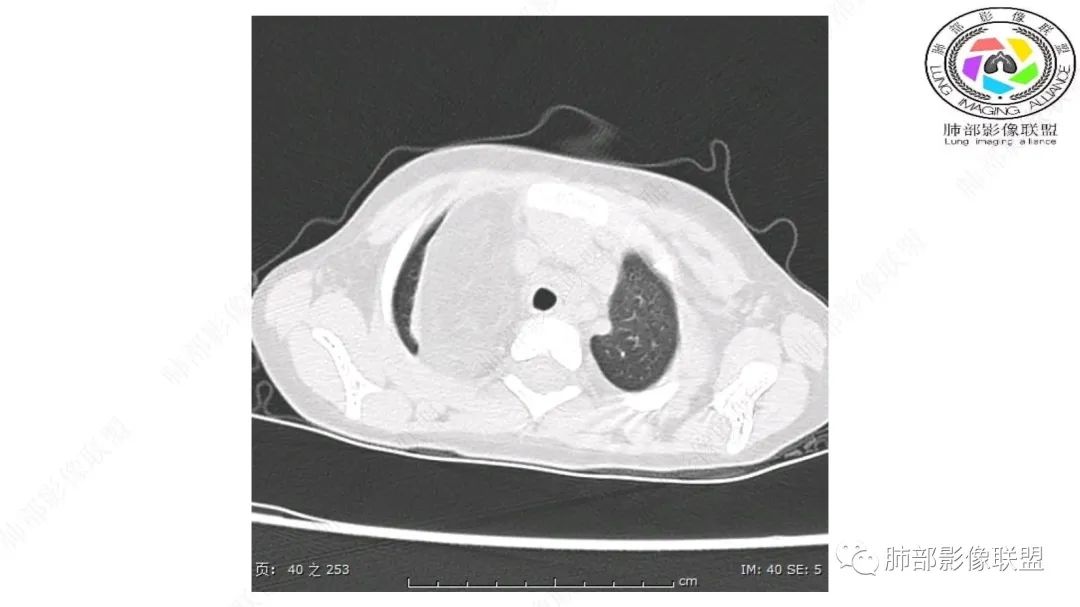

患儿3岁 咳嗽检查发现纵隔占位。右肺上叶受压表现,占位以脂肪组织密度为主,似见分隔,首先考虑为脂肪母细胞瘤,鉴别脂肪瘤,畸胎瘤。

病灶属于交界区,主体位于肺内,占位效应明显,前方突入胸壁,胸腺受压变形,胸膜显示欠清楚;病灶包绕上叶肺动脉;似乎有体动脉供血。符合肺内的点:包绕上叶肺动脉分支;符合纵隔的点:前方似乎突入胸壁,与胸腺关系比较密切,但是与上腔静脉的关系提示病灶不支持纵隔来源,前纵隔的常规会将上腔静脉受压后移、外移,这是不符合的。

1.右上肺-纵隔交界区巨块影,主体位于右肺一侧,紧贴胸腺、头臂干、右锁骨下动脉、上腔静脉、奇静脉等,不能分离,但病灶整体边界清楚。注意上述相邻腔静脉等结构未见受压变形,纵隔亦未见明显向左推移,至少提示两点:

2.肺动脉穿行也许是肺内来源最重要支持点!

CT扫描对脂肪类肿瘤常有独到价值。肿块孤立、边界清楚,未见周围浸润,较均匀脂肪样低密度,高度提示为良性!

发生于成人为脂肪瘤表现,婴幼儿自然会想到脂肪母细胞瘤。两者生物学行为并无本质区别。